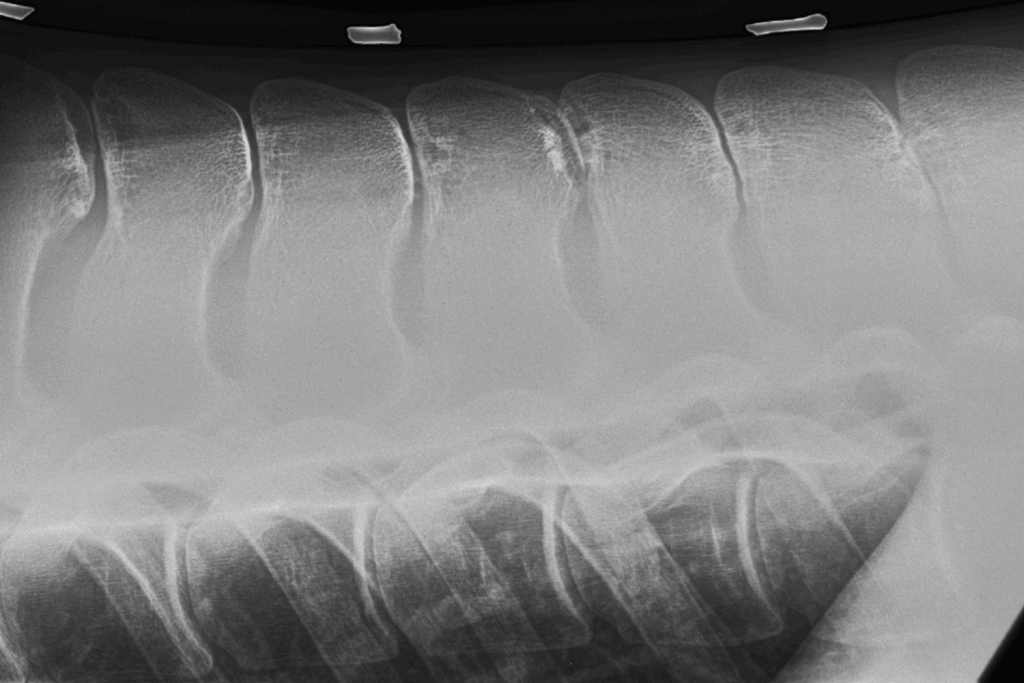

Kissing spines typically occur in the last few thoracic vertebrae—right where a. Kissing spines is most common in the thoracic region, where the saddle and the rider's weight are located

So the diagnosis must come from a careful vet who combines a change demonstrated in your horse's X-rays and tests, as well as elements of their history that indicate that. As a horse owner, understanding this condition is crucial for the health and well-being of your equine companion Kissing spine is a skeletal abnormality in horses in which bony projections on the vertebrae of the spine touch or "kiss"